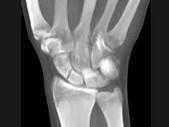

问题 男,21岁,手部不慎摔伤,局部疼痛,结合图像,最可能的诊断是?(?)

选项 A.大多角骨骨折 B.小多角骨骨折 C.三角骨骨折 D.月骨骨折 E.舟状骨骨折

答案 E